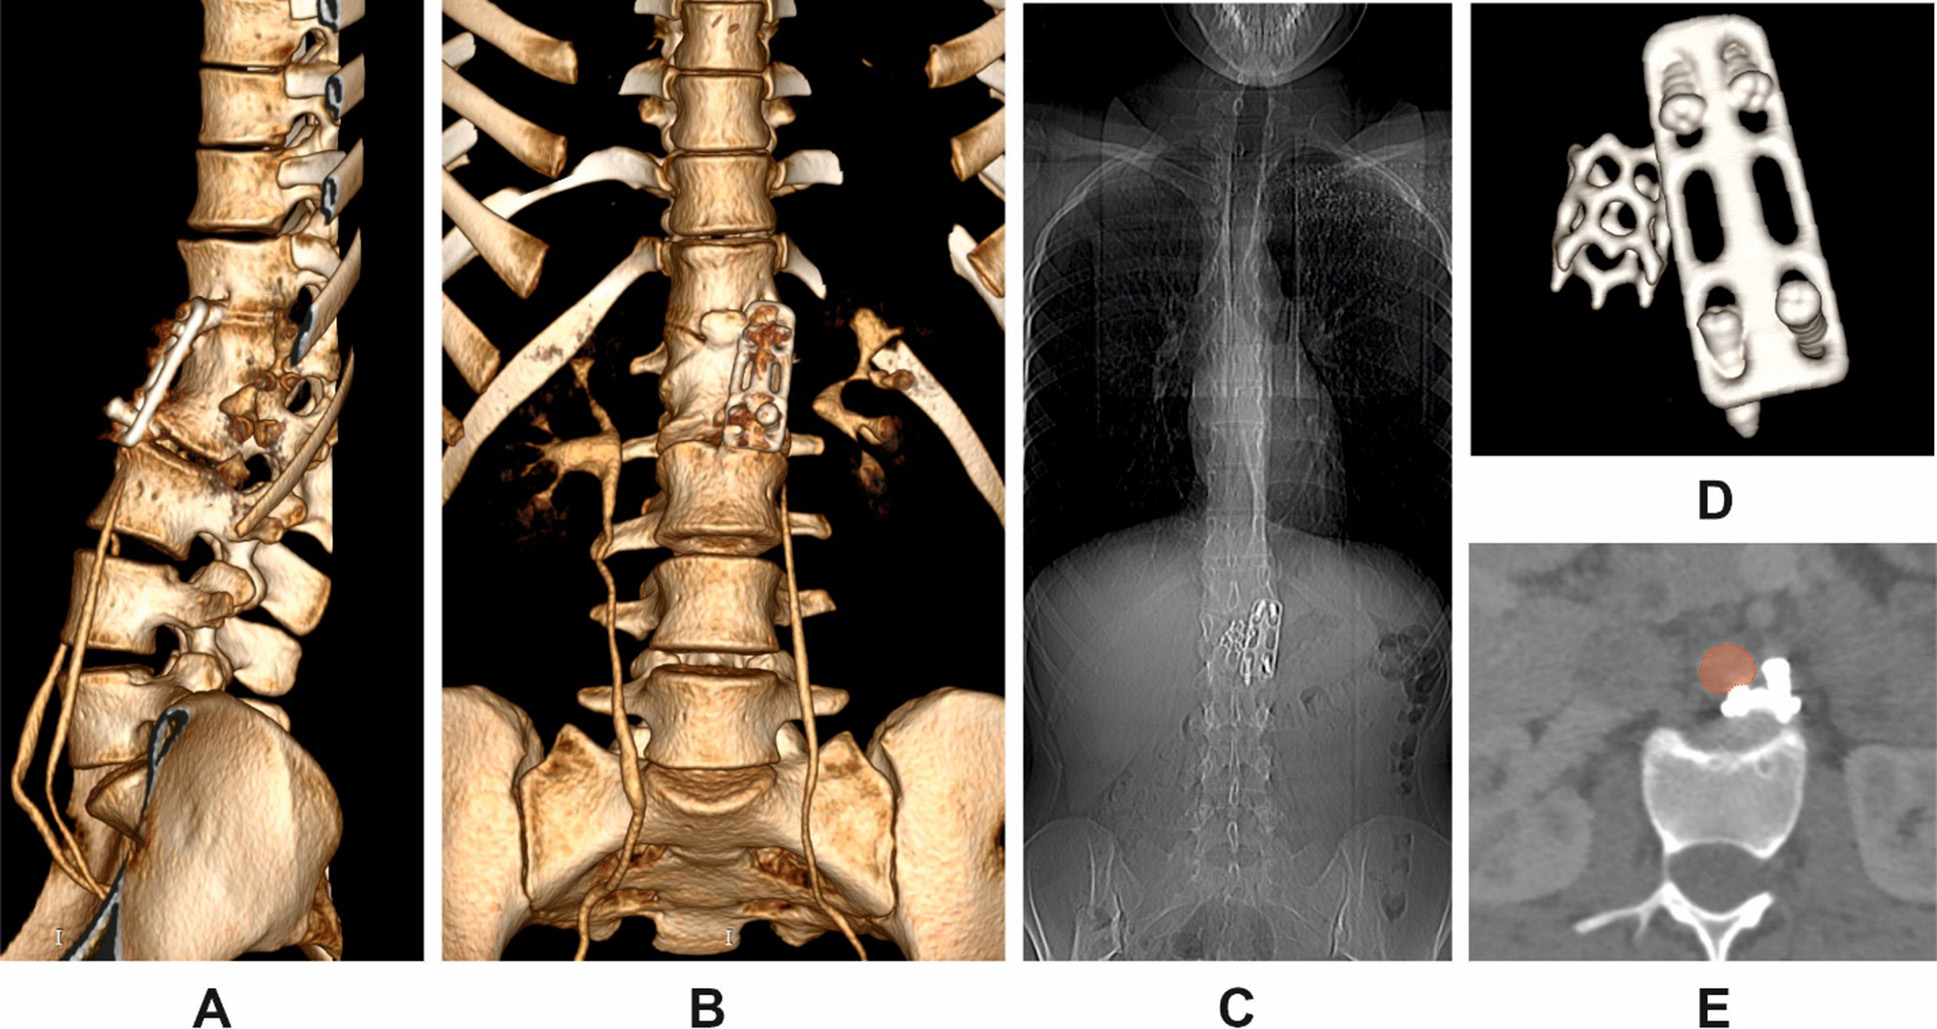

Clinical case 1

Patient K., a 19-year-old female, sustained a thoracolumbar injury in a motor vehicle accident. Сomputed tomography (CT) imaging confirmed a burst fracture of the L1 vertebral body with minor retropulsion of bone fragments into the spinal canal. The patient exhibited no neurological deficit (ASIA grade E). Surgical management consisted of partial corpectomy via a ventrolateral approach, placement of a titanium mesh cage for anterior column support, and stabilization using an anterior plate fixed to the T12 and L2 vertebral bodies with screws.

Following rehabilitation, the patient returned to full physical activity. Five years postoperatively, she began to report intermittent low back pain following physical exertion, which did not require analgesic therapy. At 7.3 years postoperatively, she developed new-onset epigastric pain. After excluding visceral causes, CT of the thoracic and lumbar spine was performed.

CT imaging revealed complete loosening and extraction of all fixation screws, along with dislocation of the anterior plate (Fig. 1 A, B, D). The migrated screws were found in direct proximity to the abdominal aorta, with one causing localized indentation of the vessel wall (Fig. 1E). A pronounced segmental kyphotic deformity at the instrumented level was noted, with a bisegmental Cobb angle between T12 and L2 measuring 39.8°. However, overall sagittal alignment was preserved, presumably due to compensatory lumbar hyperlordosis. No segmental or global coronal deformity was observed (Fig. 1B, C). Bone mineral density (BMD) was measured at 192.26 HU (SD 43.82). On clinical examination, the patient remained neurologically intact. Pain intensity was 3 out of 10 on the visual analog scale (VAS).

Fig. 1. Multiplanar CT reconstructions in Patient K.

A: 3D posterior oblique view of the thoracolumbar junction;

B: anterior 3D reconstruction;

C: anteroposterior scout view;

D: isolated 3D view of the displaced instrumentation;

E: axial view showing displaced screws in close contact with the abdominal aorta (highlighted in red)

Revision surgery was planned, including removal of the anterior implant and screws, followed by posterior transpedicular stabilization. Due to the high risk of intraoperative complications, particularly related to screw proximity to the aorta, vascular surgical backup was scheduled. However, the patient deferred the procedure indefinitely due to family circumstances.